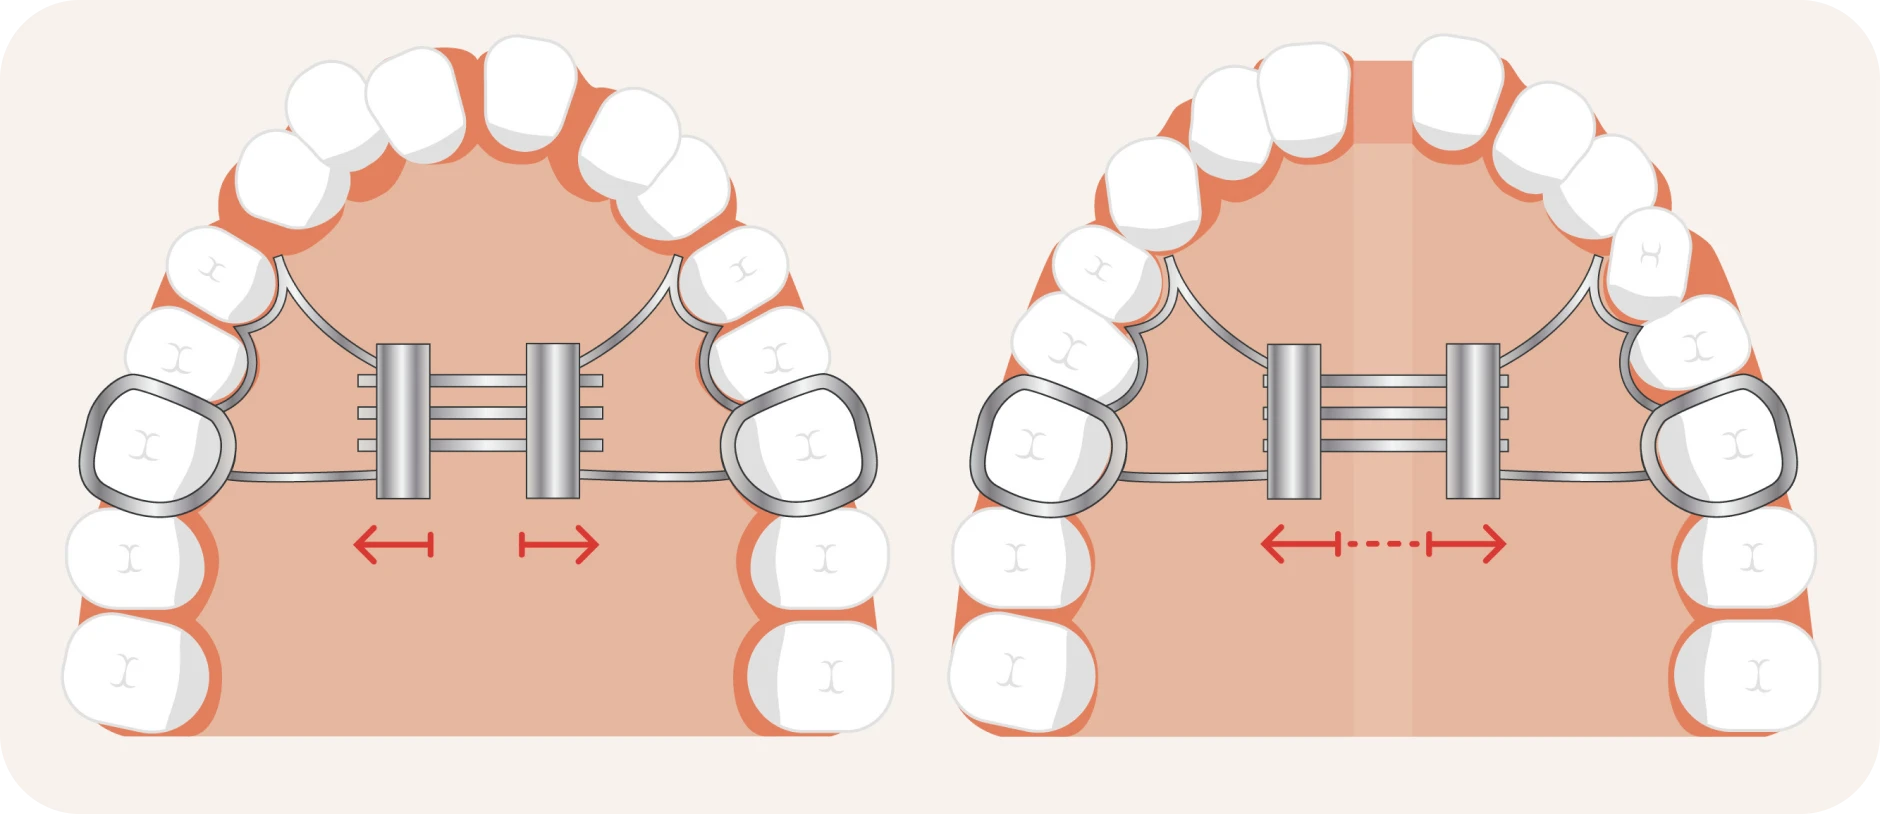

Comment fonctionne cet appareil orthodontique ?

L’orthodontiste fixe le disjoncteur sur les molaires supérieures. Un mécanisme central permet d’élargir progressivement le palais en tournant une vis de réglage. Cette activation est réalisée quotidiennement selon les instructions du praticien. Une activation progressive garantit un élargissement sans douleur excessive et respecte la croissance osseuse.

- Mode d’action du disjoncteur

Le disjoncteur applique une pression douce et constante sur les os du palais. Cette pression entraîne leur écartement progressif. Après quelques semaines, l’espace nécessaire pour les dents définitives est créé. Ce processus s’accompagne parfois de l’apparition d’un léger écart entre les incisives supérieures, un signe que le traitement fonctionne correctement.